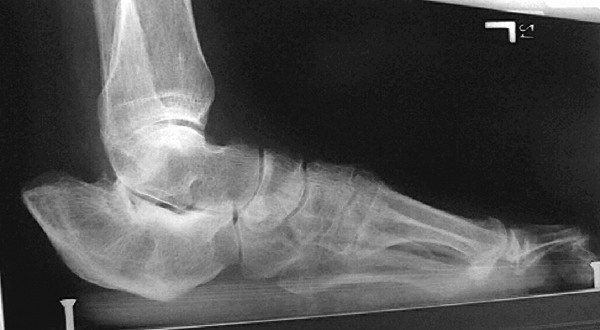

Some type of surgical intervention is often indicated for diabetic foot infections in order to minimize tissue loss, preserve foot function and manage soft tissue infection and necrosis.17 It is an integral part of wound management and, depending on the severity of the ulceration, can range from incision and local debridement to wide area ablation of tissue and amputation. Wound debridement, which is usually the first step in treating a diabetic foot infection, involves removing necrotic tissue, exudates and metabolic waste.18 The presence of exudates is most often due to an infection by a pathogen, such as S. aureus, which can produce a fibrin-rich biofilm that makes the bacterial colony more resistant to the body’s natural immune response. Surgical debridement is a quick and effective method of removing debris and necrosis. It is highly suitable for diabetic foot ulcers, which tend to have large areas of necrotic tissue and a high propensity toward infection.19 Early debridement can minimize the bacterial load, prevent and control wound infection, accelerate the healing process and ultimately help prevent a lower limb amputation. One should repeat debridement as long as new necrotic tissue continues to form.20 Debriding an ulcer also allows for better determination of wound depth, which can be difficult due to necrotic tissue or an overlying callus. However, keep in mind that wound debridement is contraindicated in cases of ischemic or neuroischemic ulcers that are not infected.20 When it comes to ulcers that are uncomplicated by gangrene, osteomyelitis or extensive soft tissue involvement, one can often treat these ulcers successfully in an outpatient setting. In one study, 58 patients with less severe infections were treated at an outpatient clinic with oral antibiotics and surgical intervention as needed. Upon evaluation, the researchers cleaned all the wounds and performed blunt or minimal sharp debridement to remove necrotic tissue and excess callus.21 Aerobic gram-positive cocci were the sole pathogen isolated in 43 percent of cases and were present in 87 percent of the cultured wounds. Nineteen patients required minor surgical procedures, which included incision and drainage, callus trimming, nail removal and sharp debridement. Initial treatment was successful in all but five infections. In an outpatient setting, Tentolouris, et. al., reported that non-limb-threatening infections caused by MRSA could also be successfully eradicated by regular debridement, dressings, patient isolation and antimicrobial therapy.14 There were similar results from a second study in which 30 percent of the wounds were infected by MRSA.16 In the absence of a systemic infection, ulcers infected by MRSA were effectively treated outside the hospital setting with regular debridement in conjunction with other therapies. Patients with either type 1 and 2 diabetes have a high prevalence of macrovascular disease.22 Due to frequent vascular dysfunction in the lower extremities and the high-pressure distribution over ulcerated areas of the foot, infections in these patients often require other surgical interventions to promote healing. Surgery may be needed to drain deep pockets of pus, which otherwise could lead to a spread of infection. In ischemic cases, a revascularization procedure is usually indicated in order to save the foot. One should attempt to treat limb-threatening infections with conservative modalities before resorting to amputation as the latter is associated with significant morbidity and mortality. In a five-year, retrospective cohort study, Pittet, et. al., evaluated outcomes of 105 patients who were admitted for foot lesions.23 Out of these patients, 74 percent had ulcers that were complicated by contiguous osteomyelitis, deep tissue involvement and/or gangrene. Although 14 patients (13 percent) required immediate amputation, researchers implemented conservative treatment in the remainder of the cohort. This consisted of daily wound dressing, debridement, bed rest, removing pressure from the affected area and parenteral antibiotics. This approach was successful in 63 percent of the remaining 91 patients. While cultures revealed the majority of infections in this cohort were polymicrobial, S. aureus was the predominant microorganism isolated.

When osteomyelitis is present in deep ulcers, aggressive debridement of devitalized bone is necessary. In a retrospective study, Bodegom et. al., analyzed the results of surgical treatment of chronic osteomyelitis in the toe of 47 patients with diabetes on antibiotic therapy.24 In all cases, they removed the metatarsophalangeal joint and 37 patients (79 percent) fully recovered after primary surgery. Seven patients required a second procedure and four patients eventually underwent an amputation. Results showed that a cure rate as high as 94 percent is possible with a combination of early surgical treatment and antibiotic therapy. When infections become limb- or life-threatening, amputation is the modality of choice. Patients with diabetes have a rate of lower extremity amputation that is 15 to 46 times higher than that of the general population and about half of these procedures are performed at the level of the foot.25,26 Fejfarova, et. al., examined the role that resistant organisms, particularly MRSA, play in the incidence of amputation.16 Out of 191 patients treated at a foot clinic, 50 (26 percent) eventually underwent varying degrees of amputation. Those who had undergone amputations were more likely to have had infected ulcers caused by resistant pathogens. Researchers found resistant strains of S. aureus in 21 percent of all patients and in 43 percent of those who required amputations. Obtaining intraoperative cultures can assist in antibiotic selection or modification. While both superficial swabbing and deep-culture biopsy yield similar results, intraoperative specimens run a lower risk of contamination. Pellizzer, et. al., found that swabbing and tissue biopsy sampling were relatively equal in reliability when comparing specimens in patients with severe polymicrobial infections.27 Both are useful for monitoring antimicrobial treatment, but deep tissue cultures appeared more sensitive for monitoring resistant pathogens.